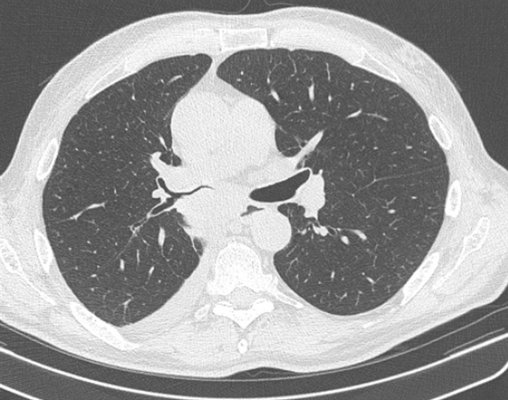

Лимфомы медиастинальной локализации не всегда диагностируются при рентгенологическом обследовании. Компьютерная томография, более детально, чем обзорная рентгенография позволяет рассмотреть конгломерат опухоли, увеличение лимфоузлов средостения, вовлечение паратрахеальных, трахеобронхиальных, прикорневых лимфатических узлов. Диагностическая значимость магнитно-резонансной томографии в верификации лимфом средостения признается не всеми авторами.

КТ ОГК. Объемное образование в средостении (патологически измененный лимфоузел), подтвержденная лимфома.